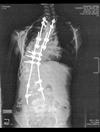

As a baby , Sam held her head cockeyed. At 4 or 5 she was diagnosed and has had at least three major back surgeries with various "hardware" inserted in an attempt to correct it.

Nothing has worked and so her last surgery was to remove some of the old hardware (first pic), insert adjustable rods and to fuse most of her vertebra.

I've include a couple of X-rays to give you an idea of Sam's situation. If you have any suggestions, recommendations etc. regarding chiropractic treatment for Sam I would appreciate it.